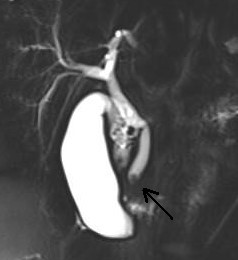

“11 yaşındaki hastamızın bilirubin yüksekliği ve şiddetli ağrısı vardı. Yapılan tetkiklerde safra yolunun taş ile tıkanmış olduğunu saptadık. Hastanemiz Gastroenteroloji Uzmanı Prof. Dr. Ethem Tankurt ile birlikte kısaca ERCP (Endoskopik Retrograd Kolanjiyo Pankreatografi) denilen kapalı ameliyat yöntemi ve sfinkterotomi uyguladığımız hastamızın bilirubini düştü ve ağrısı geçti, şifa işe taburcu oldu. Safra kesesi sadece yetişkinlerin sorunu değil, çocuklarda da görülüyor. Üstelik son 20 yılda görülme sıklığı arttı. Beslenme alışkanlıkları, bazı kan hastalıkları, ilaçlar taş oluşumunda önemli etkendir, obezite de önemli bir unsurdur. Safra kesesi taşları uzun süre bulgu vermeden kalabilir. Bazen safra kesesi iltihabına veya safra yoluna düşüp safra yolu tıkanıklıklarına neden olabilir. Safra yoluna düşmüş olan taşlar, şiddetli ağrı, sarılık ve pankreas bezi iltihaplarına yol açıp, hayati tehlike oluşturabilirler. Safra kesesi taşı, kapalı yöntemle sorunsuz bir şekilde ameliyat edilebilirken, safra yolu tıkanıklıkları endoskopi ile safra yolu girişimleri gerektirir. Çocuk ne kadar küçükse, girişim de o kadar zordur. “